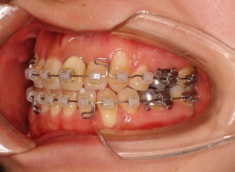

治療後(2年3ヶ月後)

歯根のパラレリング(平行性)が獲得されております。

下顎8番は、両側抜歯済みです。

顎位は良好な状態です。